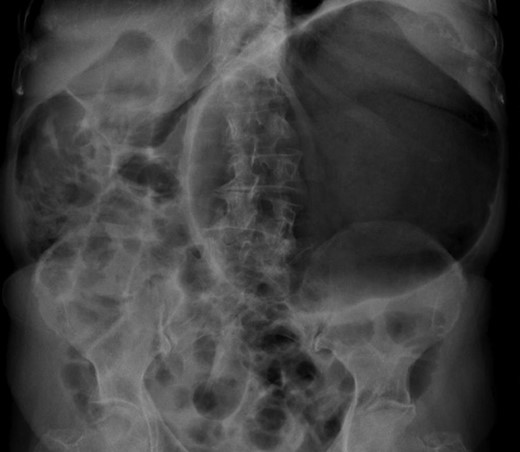

Haematological and biochemical profiling were performed, as well as plain abdominal radiographs (Fig. 4) and abdominal ultrasound, all showing no relevant changes. The upper endoscopy revealed a mild esophagitis. An upper gastrointestinal series was later executed, revealing the presence of an organoaxial volvulus (Fig. 5).

Abdominal radiograph performed during a symptomatic interval, showing no relevant changes.